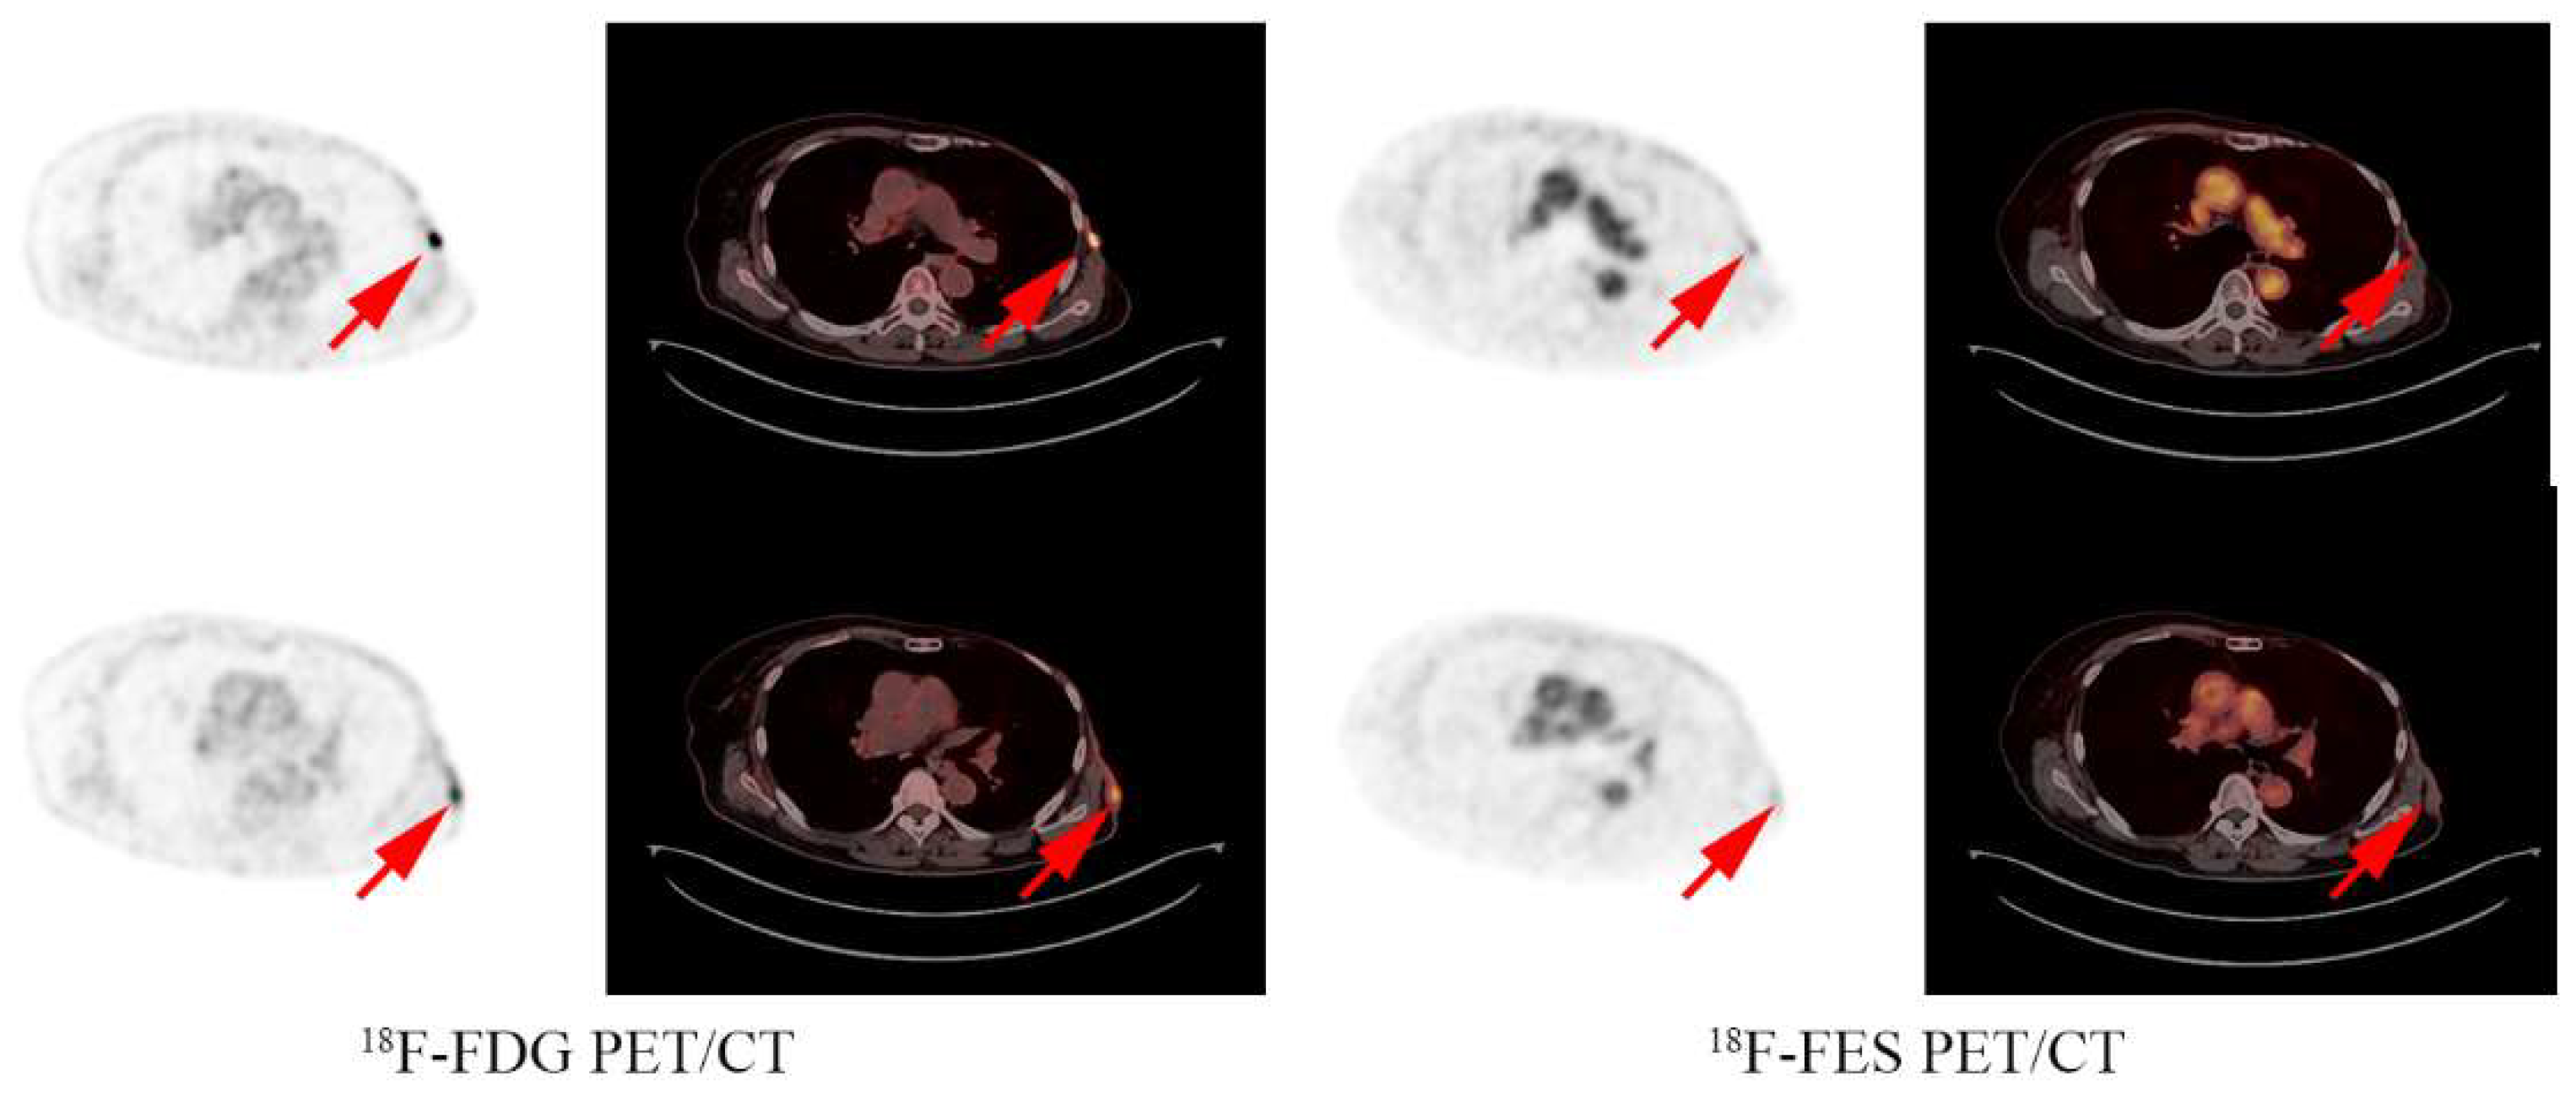

2.3. Image Interpretation

- Hao, W.; Li, Y.; Du, B.; Li, X. Heterogeneity of estrogen receptor based on 18F-FES PET imaging in breast cancer patients. Clin. Transl. Imaging 2021, 9, 599–607. [Google Scholar] [CrossRef]

- Yang, Z.; Sun, Y.; Zhang, Y.; Xue, J.; Wang, M.; Shi, W.; Zhu, B.; Hu, S.; Yao, Z.; Pan, H.; et al. Can fluorine-18 fluoroestradiol positron emission tomography-computed tomography demonstrate the heterogeneity of breast cancer in vivo? Clin. Breast Cancer 2013, 13, 359–363. [Google Scholar] [CrossRef]